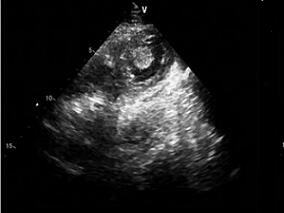

1小时条评论病史摘要:女,38岁。12年前出现间歇性胸闷、气短。4年前曾在当地医院行彩色超声心动图检查,诊断为风湿性心脏病,二尖瓣狭窄,心房纤颤。近4年来病情加重,房颤持续。近来出现呼吸困难,端坐呼吸,及双下肢水肿。 查体:心率100次/分钟,心律绝对不齐;心界明显扩...